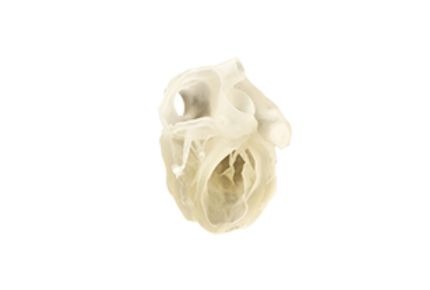

Alakítsa a sebészet jövőjét páciens-specifikus 3D modellekkel. Javítsa az előkészítést, finomítsa a műtéti technikákat, és optimalizálja az eszközöket a jobb eredmények érdekében. Az anatómiailag pontos modellek javítják a kommunikációt és rövidítik a műtéti időt.

Szerezzen gyakorlati tapasztalatot élethű modellekkel, amelyek lehetővé teszik műtéti technikák gyakorlását realista szimulációk során. Növelje a magabiztosságot összetett beavatkozásoknál, és vizsgálja a biomechanikát és patológiákat pontos másolatokkal.

Legnépszerűbb 3D nyomtató az anatómiai modellezéshez; a legszélesebb anyagválasztékkal a komplex, élethű modellekhez. Ideális minden orvosi feladatra.

Ideális sebészeti felkészüléshez, a pácienskimenetek javításához és a termékfejlesztési innováció felgyorsításához. Élethű anatómiai modellek magas biomechanikai pontossággal.

Komplex érhálózatok nyomtatása; a belső támasz könnyen vízsugaras eljárással távolítható el akár 1,0 mm átmérőjű erekből is.